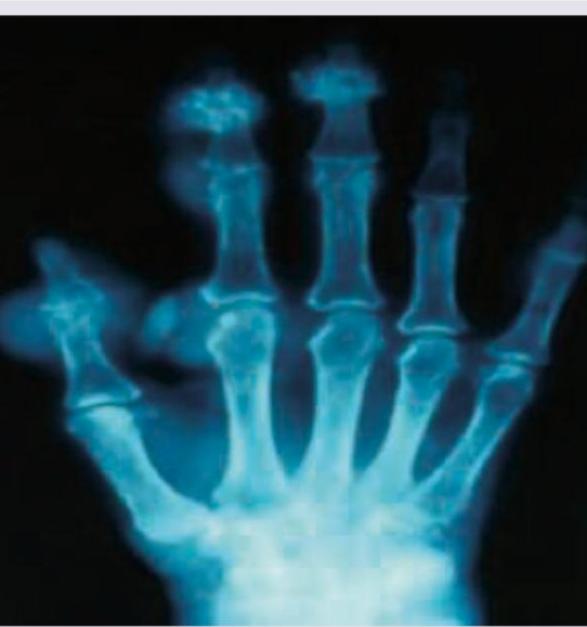

The clinical diagnosis favors development of chronic gout and the image shows presence of eccentric juxta-articular lobulated soft-tissue masses. Which of the following is the most definitive diagnostic test for gout shown in the image?

This elderly male came with a history of recurrent attacks of pain and swelling in the great toe in the past. This is the present X-ray of the hands. The diagnosis can be confirmed by:

Explanation: ***Polarized microscopy of tissue fluid aspirate*** - The definitive diagnosis of gout requires the identification of **monosodium urate crystals** in synovial fluid or tissue, typically performed with polarized microscopy. - This method directly visualizes the *negatively birefringent* (needle-shaped when perpendicular to the polarization axis) crystals, which are pathognomonic for gout. *X-ray of the joint* - X-rays can show characteristic changes in chronic gout, such as **punched-out erosions with overhanging edges** (known as Martel's sign) and soft tissue masses (tophi). - However, these findings are not specific to gout and can be seen in other conditions; they do not provide a definitive diagnosis on their own. *Blood tests for uric acid levels* - Elevated **serum uric acid levels (hyperuricemia)** are a key risk factor for gout, but they are neither necessary nor sufficient for diagnosis. - Many individuals with hyperuricemia never develop gout, and some patients can have normal uric acid levels during an acute gout attack. *MRI of the affected joint* - MRI can visualize soft tissue abnormalities like **tophi**, bone erosions, and inflammatory changes, offering detailed anatomical information. - While useful for assessing disease extent and complications, MRI cannot definitively identify the specific crystal deposits that confirm gout.

Explanation: ***Polarized microscopy of tissue fluid aspirate*** - The patient's history of recurrent pain and swelling in the **great toe**, along with the X-ray findings (which likely show features of crystal deposition such as **erosions with overhanging edges** or joint damage), is highly suggestive of **gout**. - **Gout** is definitively diagnosed by identifying **negatively birefringent needle-shaped urate crystals** within the synovial fluid or tissue aspirate under polarized microscopy. *HLA B27* - **HLA-B27** is a genetic marker associated with **spondyloarthropathies**, such as Caucasians with ankylosing spondylitis and psoriatic arthritis, not typically used for diagnosing gout. - While some spondyloarthropathies can affect the great toe, the clinical presentation and X-ray findings (which are presumably related to crystal deposition) are not characteristic of this condition. *Anti-CCP antibodies* - **Anti-CCP antibodies** (anti-cyclic citrullinated peptide antibodies) are a specific serological marker for **rheumatoid arthritis**. - Rheumatoid arthritis typically affects small joints symmetrically but does not primarily present with acute, recurrent painful swelling of the great toe or the characteristic X-ray changes seen in gout. *X-ray of lumbosacral spine* - An **X-ray of the lumbosacral spine** is indicated for conditions affecting the spine, such as ankylosing spondylitis or disc herniation. - While chronic gout can sometimes affect the spine, it is not the primary diagnostic tool for confirming gout, especially given the classic peripheral joint involvement.